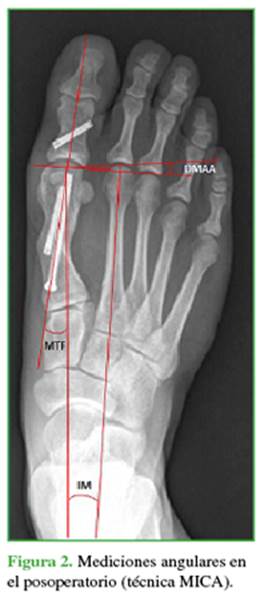

Las mediciones radiográficas después de la cirugía estuvieron a cargo de cirujanos que no habían operado al paciente (Figuras 1 y 2). De esta manera, se evaluó la pérdida o no de la corrección en ambas técnicas quirúrgicas. Todas las imágenes fueron digitales, con un programa computarizado (MB Rouler® versión 4.0), se calcularon los siguientes parámetros: a) el ángulo MTF, b) el ángulo IM usando la técnica de medición de Miller16 y c) el ángulo AMD, según la técnica mencionada por Deenik y cols.17

1)    El promedio de corrección para los ángulos MTF, IM y AMD fue de 16,83°; 1,8° y 2,06° a las 6 semanas; y de 15,8°; 1,6° y 1,98° a los 6 meses, respectivamente.

2)    La diferencia entre el ángulo IM preoperatorio y a las 6 semanas de la cirugía fue estadísticamente significativa (p <0,005), al igual que entre el preoperatorio y a los 6 meses de la cirugía (p <0,005). La relación entre la corrección IM lograda a las 6 semanas y los 6 meses no fue estadísticamente significativa (p = 0,324). Esto muestra que no hubo pérdida de corrección significativa.

3)    Las diferencias entre el ángulo MTF preoperatorio y a las 6 semanas de la cirugía, así como entre el preoperatorio y a los 6 meses de la cirugía fueron estadísticamente significativas (ambas p <0,005). La relación de corrección del ángulo MTF entre la semana 6 y el mes 6 posoperatorios fue estadísticamente significativa (p = 0,010), lo que habla de una pérdida de corrección MTF con la técnica MICA.

4)    En cuanto a la corrección del AMD, la relación entre el preoperatorio y a las 6 semanas y los 6 meses posoperatorios fue significativa en ambas mediciones (p <0,005). La pérdida de corrección entre las 6 semanas y los 6 meses de la cirugía no fue significativa (p = 0,57). No hubo pérdida de corrección.

a)    La pérdida promedio de corrección del ángulo IM fue de 0,17° entre las 6 semanas y los 6 meses (p = 0,32; no significativo).

b)    La pérdida promedio de corrección del ángulo MTF fue de 1° entre las 6 semanas y los 6 meses (p = 0,01; significativo).

c)    La pérdida promedio de corrección del ángulo AMD fue de 0,08° entre las 6 semanas y los 6 meses (p = 0,57).

d)    En cuanto a la corrección final a ángulos normales: (Figuras 8-10)

-    El 77,8% presentó ángulos IM normales a los 6 meses de la cirugía. Ocho tenían ángulos de entre 11° y 15° (22,2% restante).

-    Todos tenían ángulos MTF normales a los 6 meses de la cirugía.

-    Todos tenían ángulos AMD normales a los 6 meses de la cirugía.